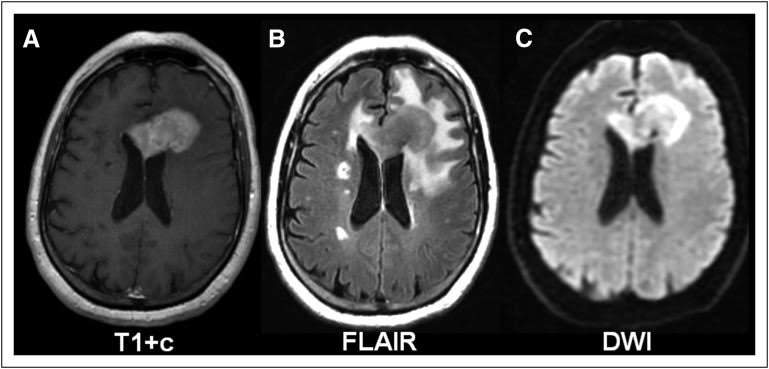

Modern imaging methods are used for diagnosis of lymphoma in the brain (cerebral lymphoma).By using cranial computed tomography (CCT) and the magnetic resonance imaging (MRI), the affected regions are clearly visible through the enriched contrast agent there.